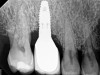

Fig 6. Radiographic bone loss confirmed the diagnosis of peri-implantitis.

Figure 6